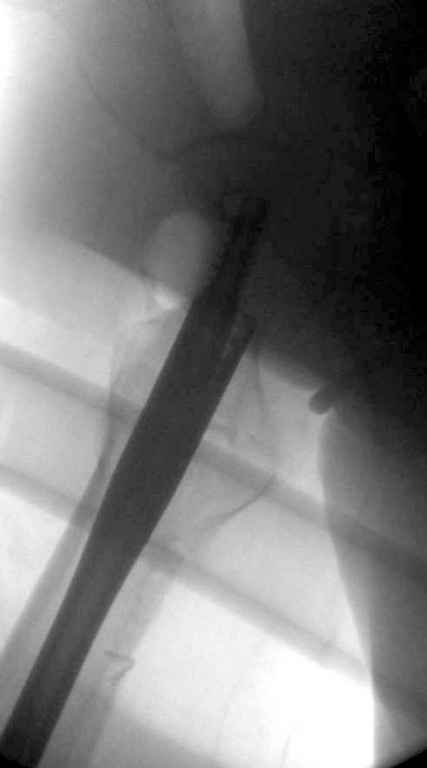

До выхода блокируемых гвоздей для фиксации косых подвертельных переломов в основном применяли Blade Plate. За счет уникальной конструкции создавался Fixed Angled Device, который соединял головку с диафизом, минуя зону перелома.

За счет особой конструкции клинка и подпорки (buttress) в диафиз создавалась стабильность, и предупреждалось скольжение по линии перелома. Перпендикулярная поверхность клинка предупреждала сгибательные и разгибательные смещения, и в сравнении с круглым винтом редко происходило прорезыванием.